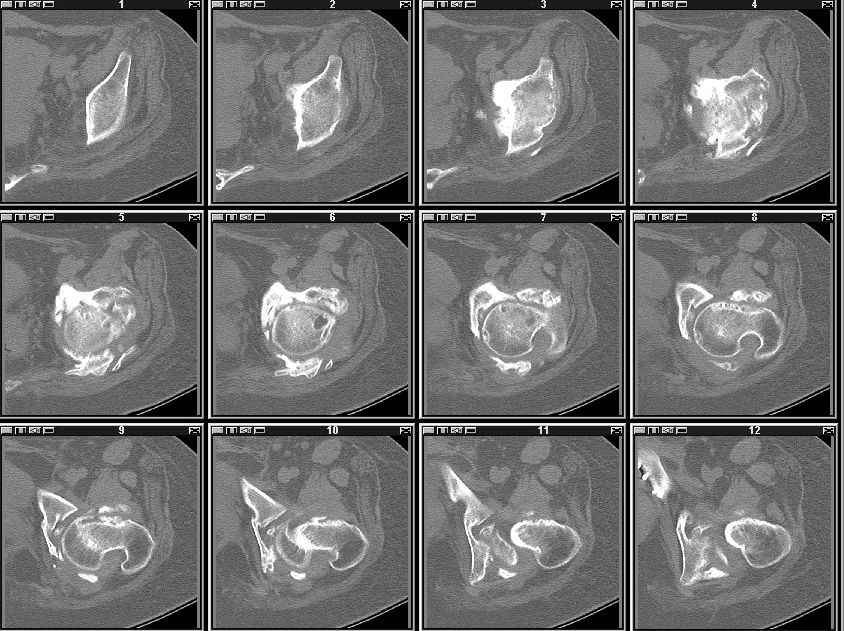

Re: Застарелое повреждение таза

высылаю КТ